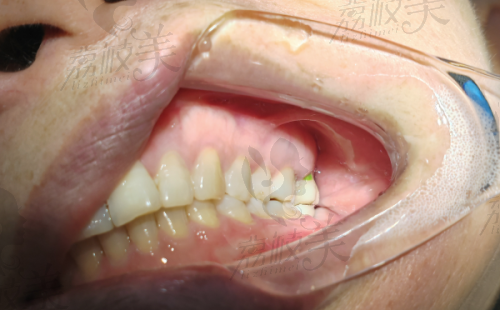

?@广州 45岁王先生:我骨量少,国内品牌说得植骨,结果卡尔斯的短体种植直接搞定,省钱还少受罪!